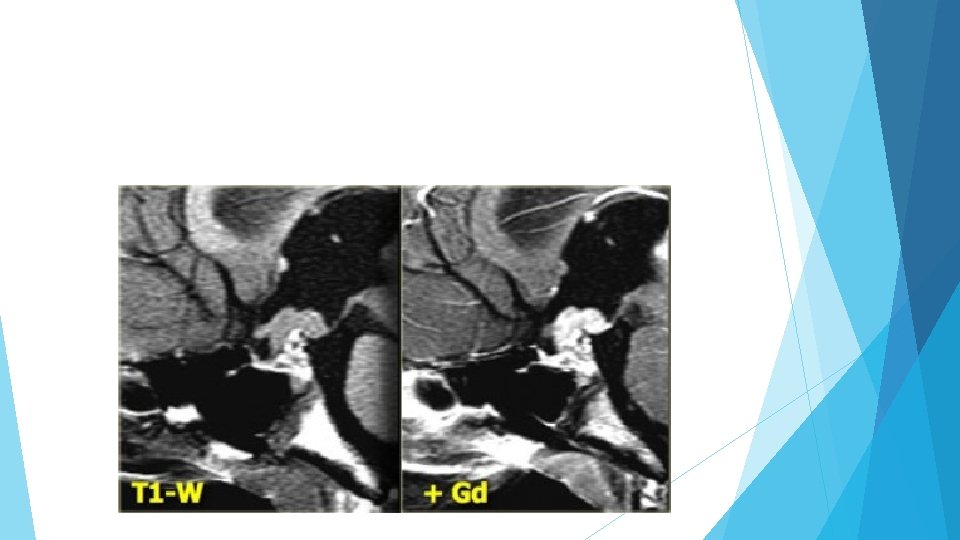

Thrombosed aneurysm On the left the T 1 -weighted image of a thrombosed aneurysm with high signal intensity on the unenhanced scan. It originates in the intracavernous segment of the right internal carotid artery. On the right the T 2 weighted images: the thrombosed aneurysm has a dark rim.

Partially thrombosed aneurysm